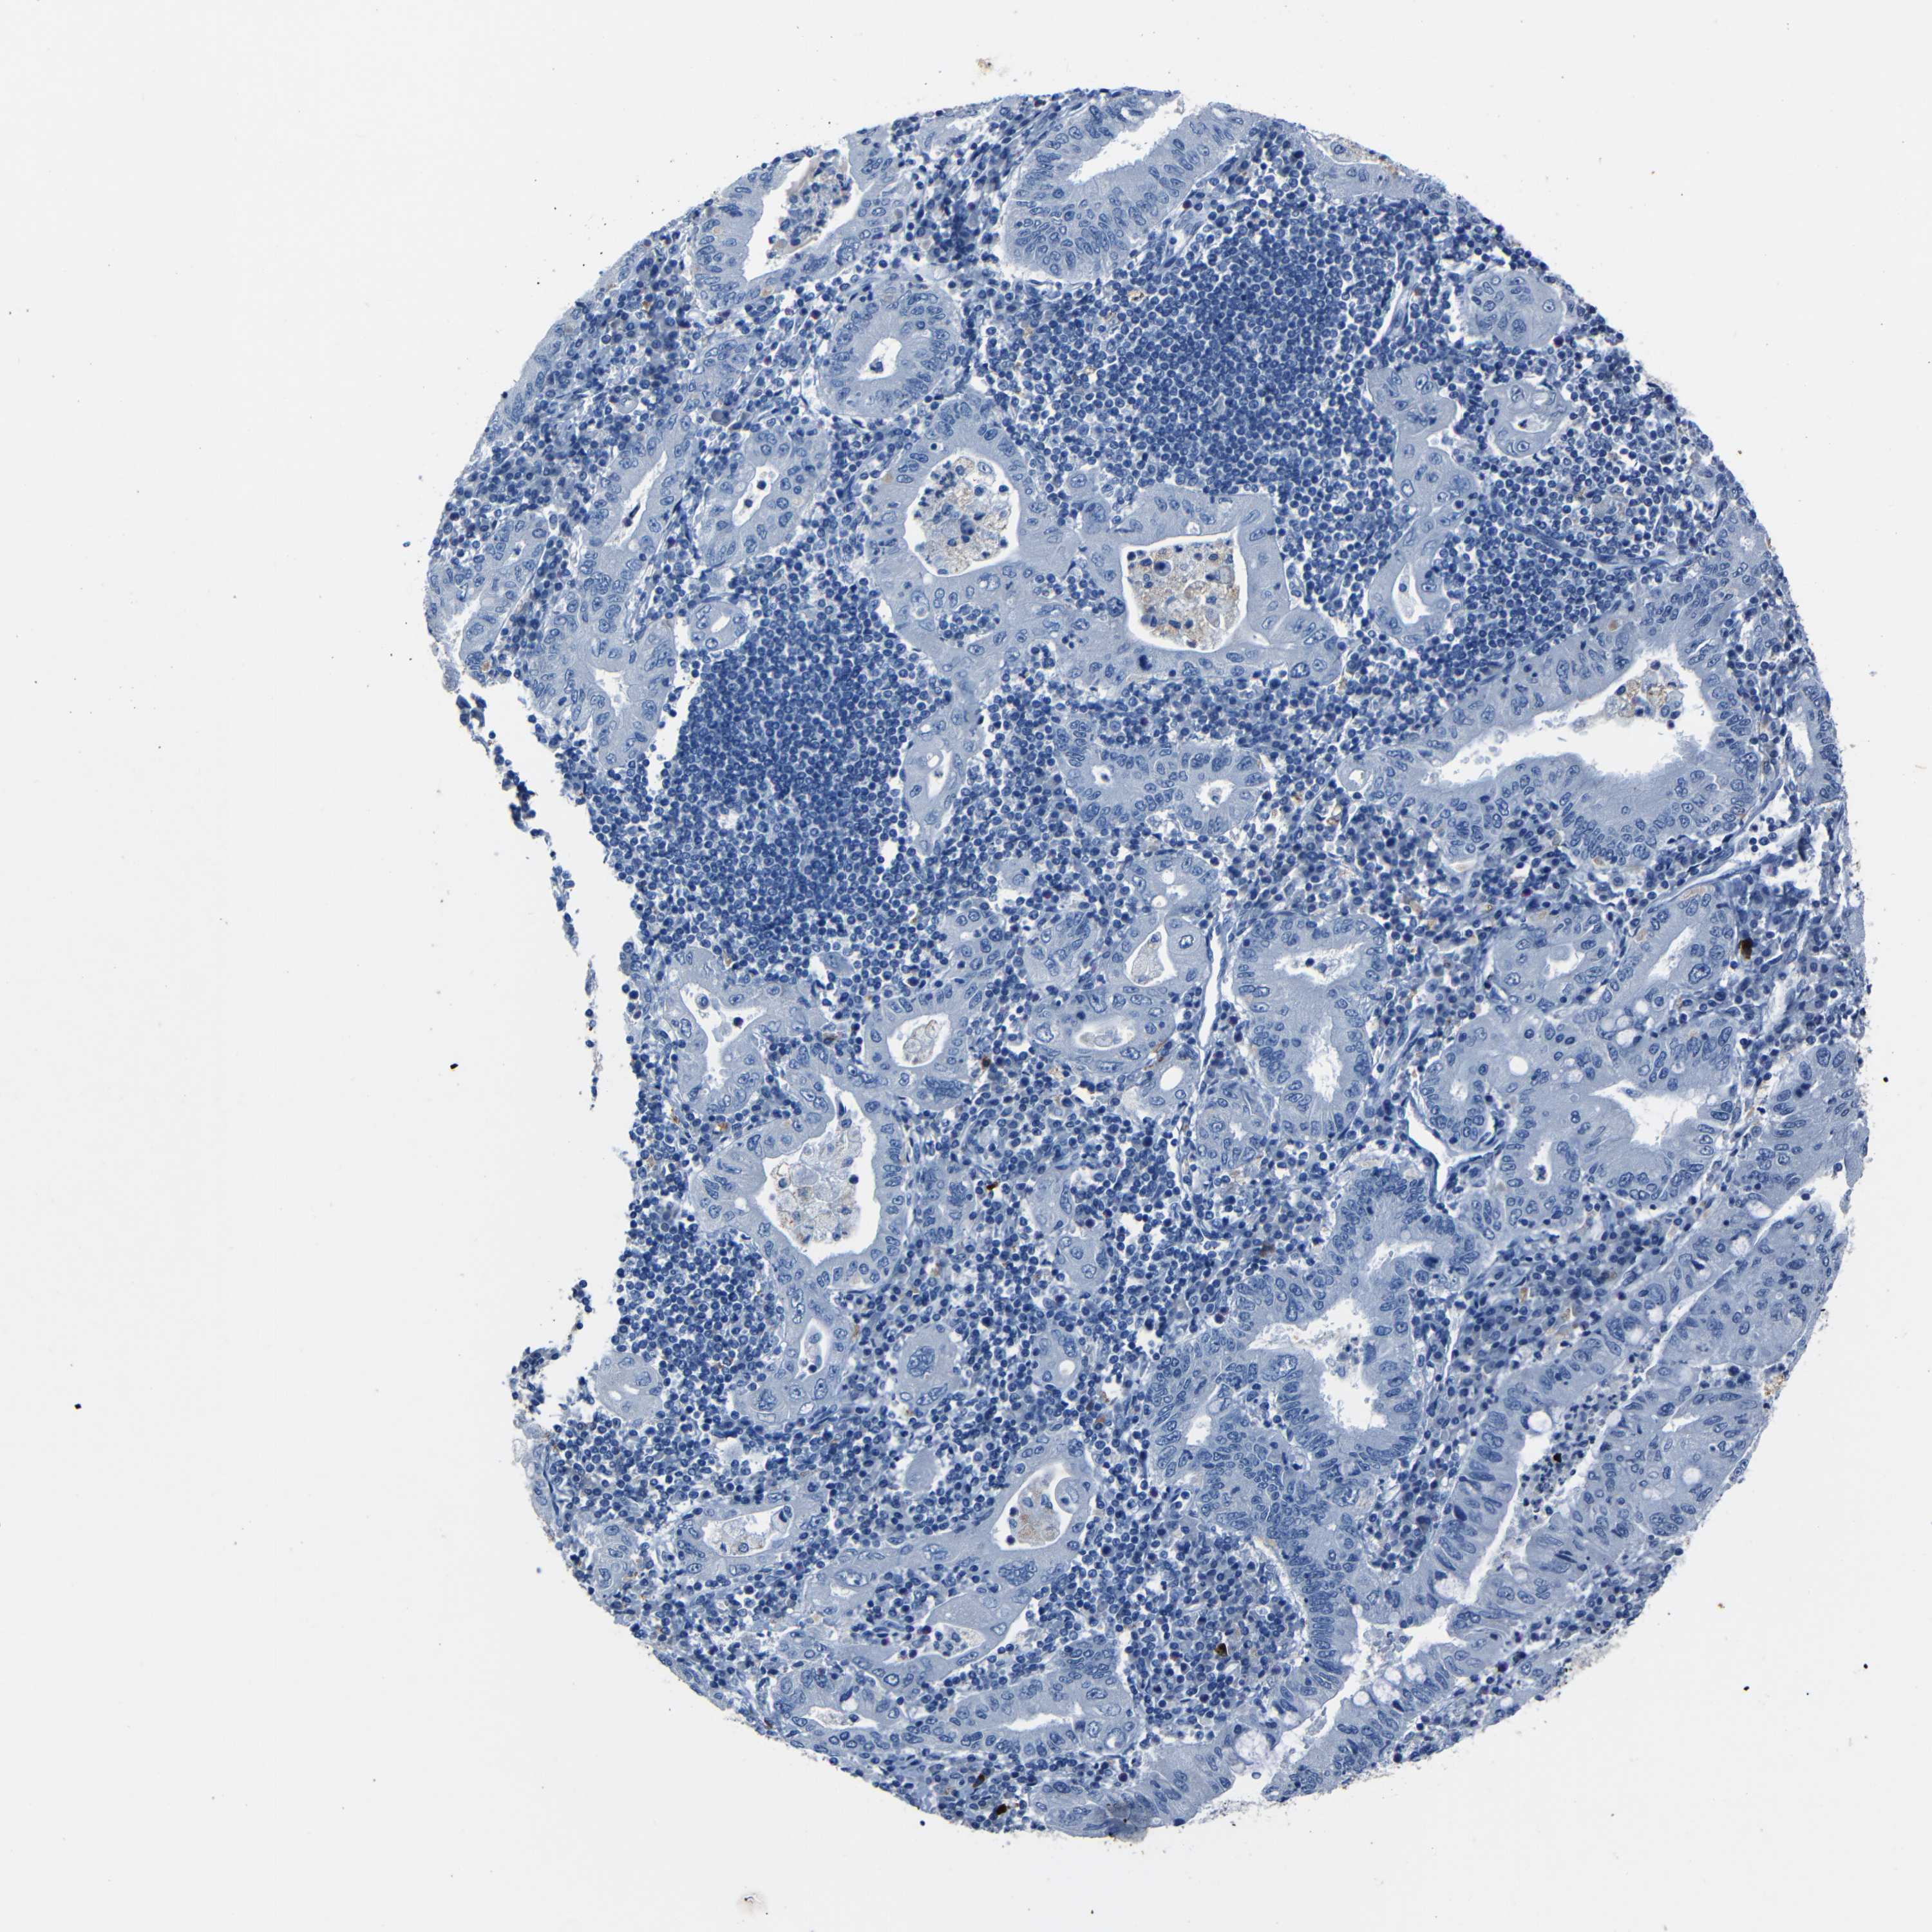

STOMACH CANCER - Protein expressioni

A mouse-over function shows sample information and annotation data. Click on an image to view it in a full screen mode. Samples can be filtered based on level of antibody staining by selecting one or several of the following categories: high, medium, low and not detected. The assay and annotation is described here.

Antibody stainingi

Antibody staining in the annotated cell types in the current human tissue is reported as not detected, low, medium, or high, based on conventional immunohistochemistry profiling in selected tissues. This score is based on the combination of the staining intensity and fraction of stained cells.

Each image is clickable and will lead to virtual microscopy that enables deeper exploration of all samples and also displays staining intensity scores, fraction scores and subcellular localization as well as patient and tissue information for each sample.

Adenocarcinoma, NOS

Adenocarcinoma, High grade